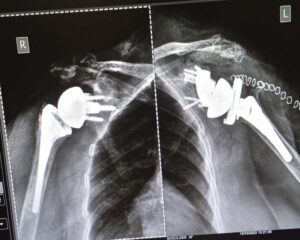

The customized implant was successfully implanted, achieving stable fixation and accurate glenoid reconstruction. Postoperative imaging confirmed proper implant positioning with a stable foundation for reverse shoulder arthroplasty.